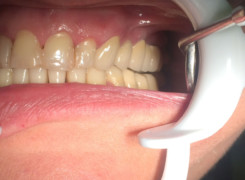

Pan Ryszard trafił do Naszego Gabinetu z jasno sprecyzowanym oczekiwaniem. Miał 84 lata i chciał odzyskać możliwość swobodnego spożywania posiłków oraz poprawienia sobie komfortu życia a także prosił aby przywrócić mu piękny uśmiech jakim cieszył się przed laty. Już na początku pierwszej rozmowy zastrzegł, że interesuje go wyłączenie rozwiązanie uzupełnieniem protetycznym stałym. Nie miał zamiaru użytkować żadnych protez ruchomych. Mając na uwadze powyższe wykonaliśmy Panu Ryszardowi zdjęcie pantomograficzne oraz badanie tomograficzne szczęki i żuchwy na postawie których zapanowywaliśmy Pacjentowi optymalne rozwiązanie – stałe uzupełnienie protetyczne w postaci 28 koron cyrkonowych zamontowanych do dwóch belek cyrkonowych które będą przymocowane do 16 implantów w konfiguracji 8 wszczepów w szczęcie 8 w żuchwie. Po omówieniu powyższego planu przystąpiliśmy do Wspólnej pracy której efekty w poszczególnych etapach prezentujemy poniżej.